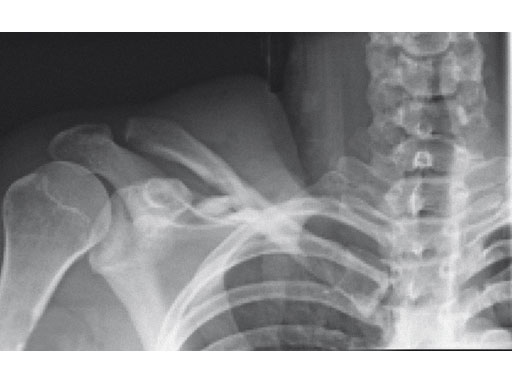

A 22-year-old man sustained an open clavicle fracture after a motorcycle injury.

Fig 1ab Preoperative x-rays.

Fig 2ab Postoperative images.

Fig 3ab X-rays taken 3 months postoperatively.

Case provided by Harry A Hoyen III, Cleveland, USA